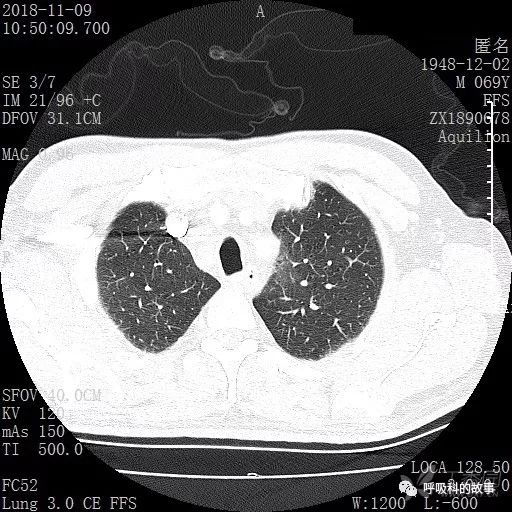

胸部增强CT示右肺门占位伴远端阻塞性肺炎,纵膈、右肺门、右侧颈根部、右侧腋下及肝门部肿大淋巴结。两侧胸腔少量积液。

肺窗CT